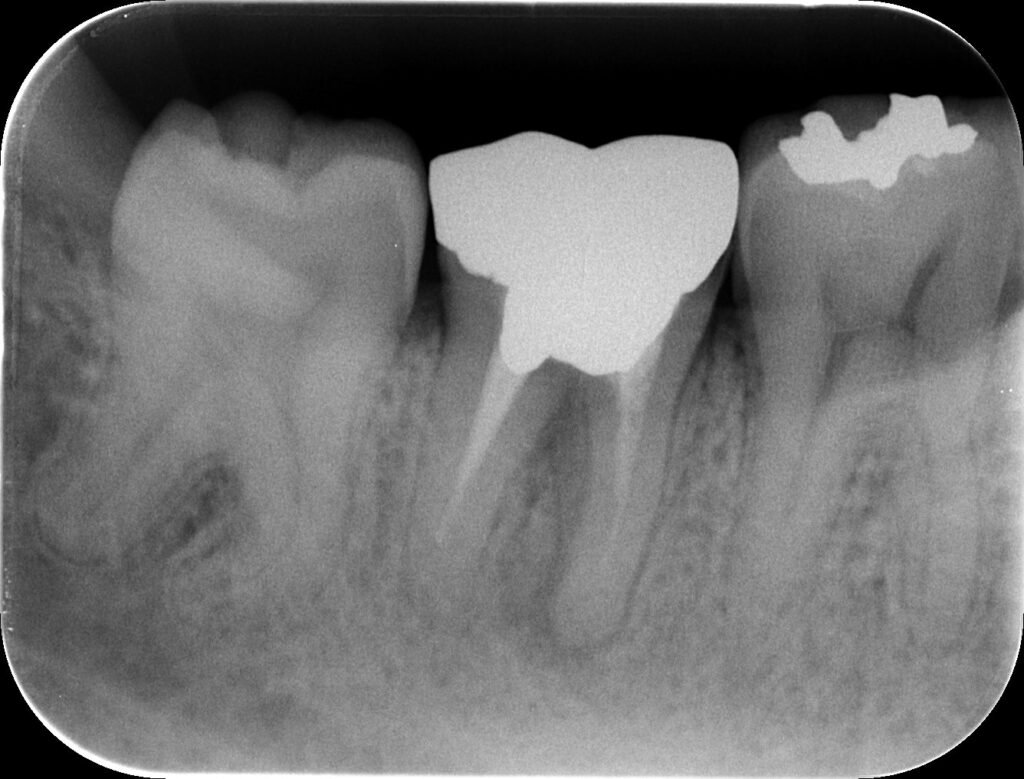

PA(2023.12.20)

近心根に根尖病変が見える。

そして、ほとんど根管形成はなされていない。

ということは、再根管治療に勝機はある。

が、

Sinus tractの存在がどう影響するか?

遠心根にはほぼ病変はないようだ。

ここは、再根管形成も不要と考えてもいいだろう。

ということで、この歯の治療は再根管治療だ。

そして、

M根のみを攻略すればいいとわかる。

それが、

Selective Root Canal Retreatment

である。